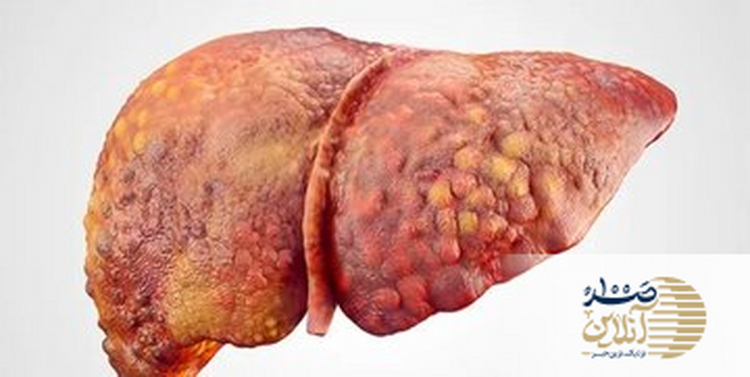

بهنقل از صد آنلاین،کبد یکی از اعضای حیاتی بدن است که نقش مهمی در سلامت کلی ایفا میکند. این عضو مسئول تولید پروتئین، مدیریت کلسترول و سمزدایی از مواد مضر است. به همین دلیل، حفظ سلامت کبد برای یک زندگی سالم ضروری است. در این مقاله، به بررسی ۸ ماده غذایی میپردازیم که میتوانند به حفظ و بهبود سلامت کبد کمک کنند.